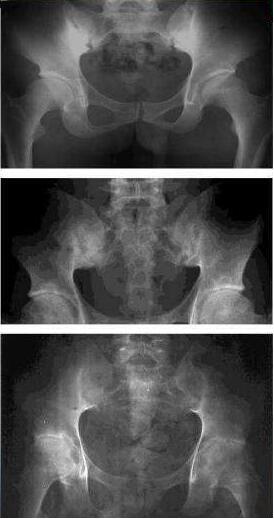

強直性脊柱炎是主要以脊柱為主要病變部位的慢性病,累及全身中樞大關(guān)節(jié),引起脊柱強直和纖維化,造成不同程度眼、肺、肌肉、骨骼病變,屬自身免疫性疾病。

強直性脊柱炎除了脊椎關(guān)節(jié)發(fā)炎所帶來的疼痛之外,還會因為結(jié)締組織鈣化,導(dǎo)致脊椎有效性的僵硬變形。若再有骨質(zhì)流失加上應(yīng)力異常集中的結(jié)果,會造成脊柱多處骨折。